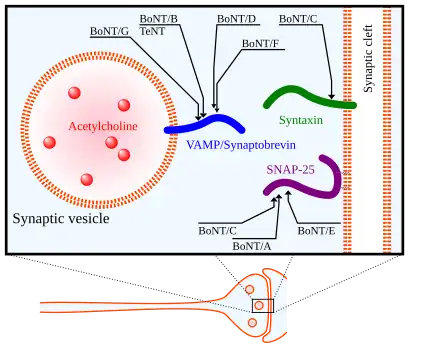

There are 8 known isotypes of BoNT, BoNT/A – BoNT/H, each with different specific cleavage sites on SNARE proteins. SNAP25, a member of the SNARE protein family located in the membrane of cells, is cleaved by BoNT isotypes A, C, and E. The cleavage of SNAP-25 by these isotypes of BoNT greatly inhibits their function in forming the SNARE complex for fusion of vesicles to the synaptic membrane. BoNT/C also targets Syntaxin-1, another SNARE protein located in the synaptic membrane. It degenerates these Syntaxin proteins with a similar outcome as with SNAP-25. A third SNARE protein, Synaptobrevin (VAMP), is located on cell vesicles. VAMP2 is targeted and cleaved by BoNT isotypes B, D, and F in synaptic neurons.[35] The targets of these various isotypes of BoNT as well as Tetanus Neurotoxin (TeNT) are shown in the figure to the right.

In each of these cases, Botulinum Neurotoxin causes functional damage to SNARE proteins, which has significant physiological and medical implications. By damaging SNARE proteins, the toxin prevents synaptic vesicles from fusing to the synaptic membrane and releasing their neurotransmitters into the synaptic cleft. With the inhibition of neurotransmitter release into the synaptic cleft, action potentials cannot be propagated to stimulate muscle cells. This result in paralysis of those infected and in serious cases, it can cause death. Although the effects of Botulinum Neurotoxin can be fatal, it has also been used as a therapeutic agent in medical and cosmetic treatments.[40][41]